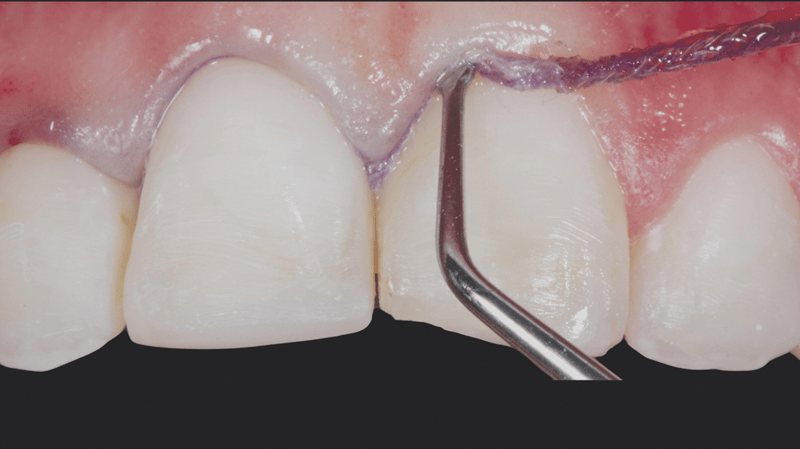

- Gingivale Sulkuspräparation: Legen eines gestrickten Ultrapak™ Retraktionsfadens (Größe 0) in den gingivalen Sulkus, zwecks Vorbereitung des Ätzvorgangs.

- Ätzen des unpräparierten Schmelzes: Ätzen des unpräparierten Schmelzes mit Hilfe von Ultra-Etch Ätzgel mit 35% Phosphorsäure (30 Sekunden).

- Adhäsiv-Applikation und -Ausdünnung: Applikation von Peak Universal Bond Adhäsiv, verblasen mit einem Luftstrahl zu einer dünnen Schicht und anschließende Absaugung.

- Zementieren: Zementieren der Veneers mit PermaShade™ LC Befestigungskomposit (Farbe Translucent) (in Europa nicht verfügbar).